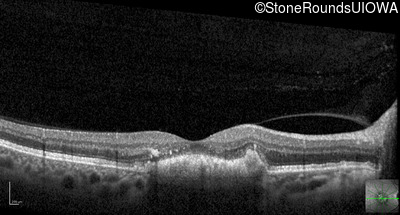

Optical Coherence Tomography - Right - 20/40 -1

Exemplar / OCT Stack